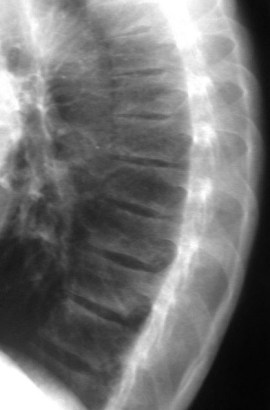

SIGNO DE LA ALMOHADILLA DEL TALÓN

El engrosamiento de los tejidos blandos del talón mayor de 23 mm es un signo de acromegalia, aunque no es específico, ya que también puede verse por obesidad, edema periférico, mixedema , traumatismo o infección del talón. La radiografía corresponde a un paciente con acromegalia.

Otro ejemplo del signo de la almohadilla grasa del talón en una fractura del calcáneo.

Referencias: Steinbach HL, Russell W. Measurement of the heel-pad as an aid to diagnosis of acromegaly. Radiology 1964; 82: 418-423. En: http://pubs.rsna.org/doi/abs/10.1148/82.3.418.

http://www.gentili.net/signs/12.htm.